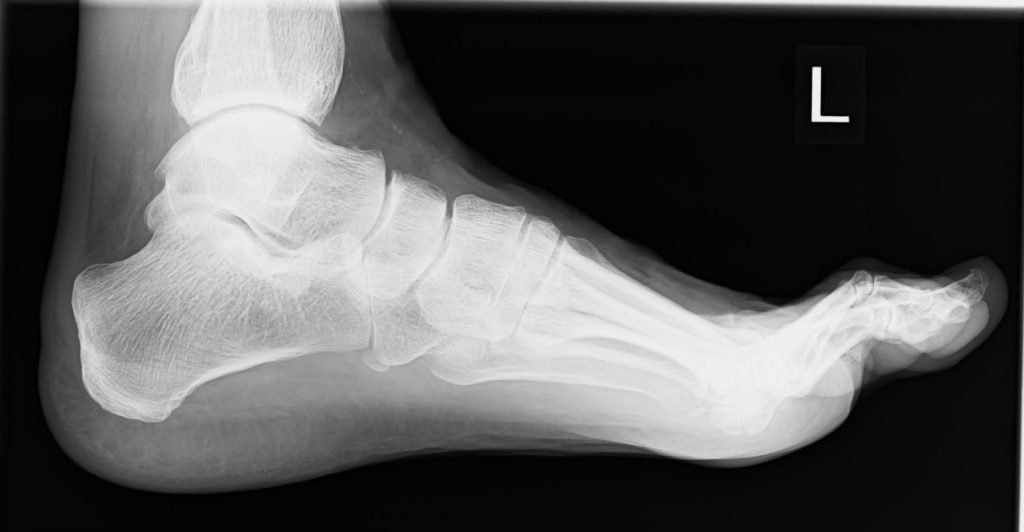

- Röntgen zur Beurteilung von Gelenkspalt, Osteophyten, Stellung

Der Hallux rigidus ist eine Arthrose des Großzehengrundgelenks (MTG I). Knorpelverschleiß und knöcherne Anbauten (Osteophyten) führen zu Schmerzen und Bewegungseinschränkung – häufig zuerst beim Abrollen. Abgrenzung zu verwandten Krankheitsbildern:

Arthrodese (Gelenkversteifung, fortgeschrittene Arthrose)

Versteifung des Großzehengrundgelenks in funktioneller Position. Sehr verlässliche Schmerzausschaltung auf Dauer, stabiles Abrollen, gute Belastbarkeit im Alltag und für viele Sportarten.